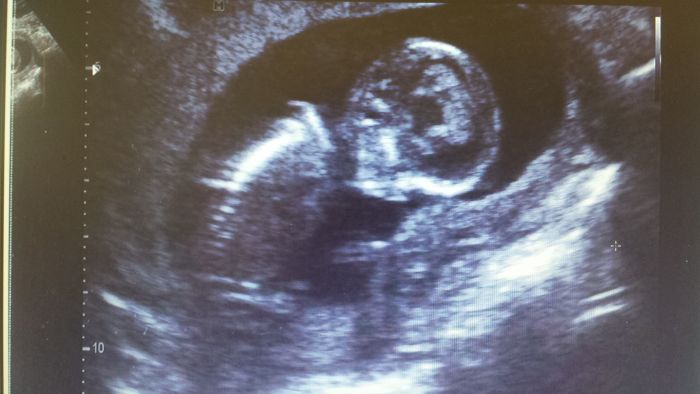

Zkousim vlozit fotku, v tydnu jsem se moc nedostala k PC a z mobilu mi to neslo. Je to fotka od me doktorky ze stredy, kdy jsem byla 13+3. Prcek mel na sreeningu 7cm. Hlavicka od ucha k uchu 2,4 cm.